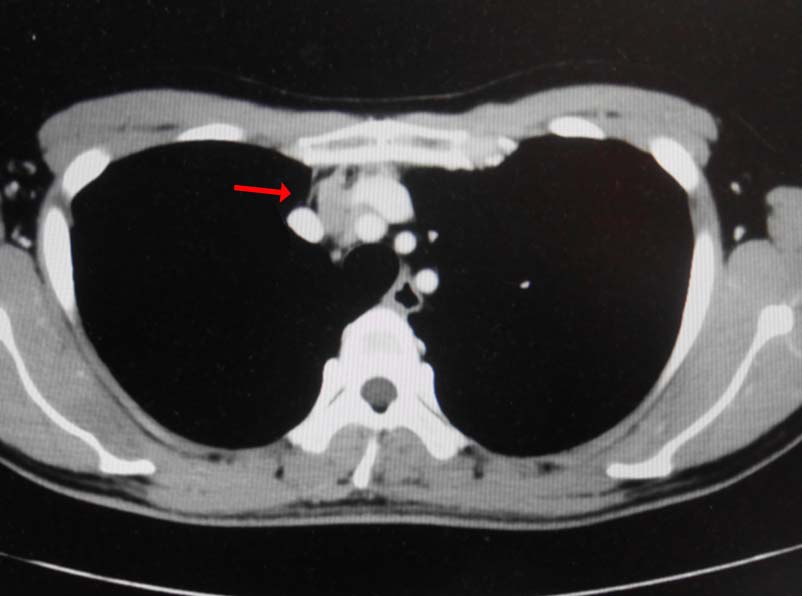

無痛性精巣腫大で泌尿器科受診. 画像診断では, 左精巣最大径4.5cmの腫瘤で縦隔リンパ節転移が疑われた. 左高位精巣摘除術をうける.

前縦隔や右心横隔膜角部に不定形, 不均一でべたっとした腫瘤状軟部濃度域を認める. 節外浸潤を伴ったリンパ節転移の可能性を考える.

画像: 左精巣腫瘤. 縦隔リンパ節転移疑い.